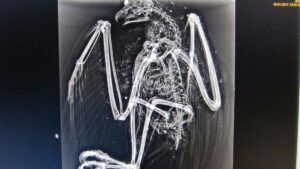

Los vigilantes de seguridad del aeropuerto han hallado cerca de las instalaciones aeroportuarias de Palma un ejemplar de águila pescadora, ‘Pandion haliaetus’, con numerosos perdigones en su interior. 325